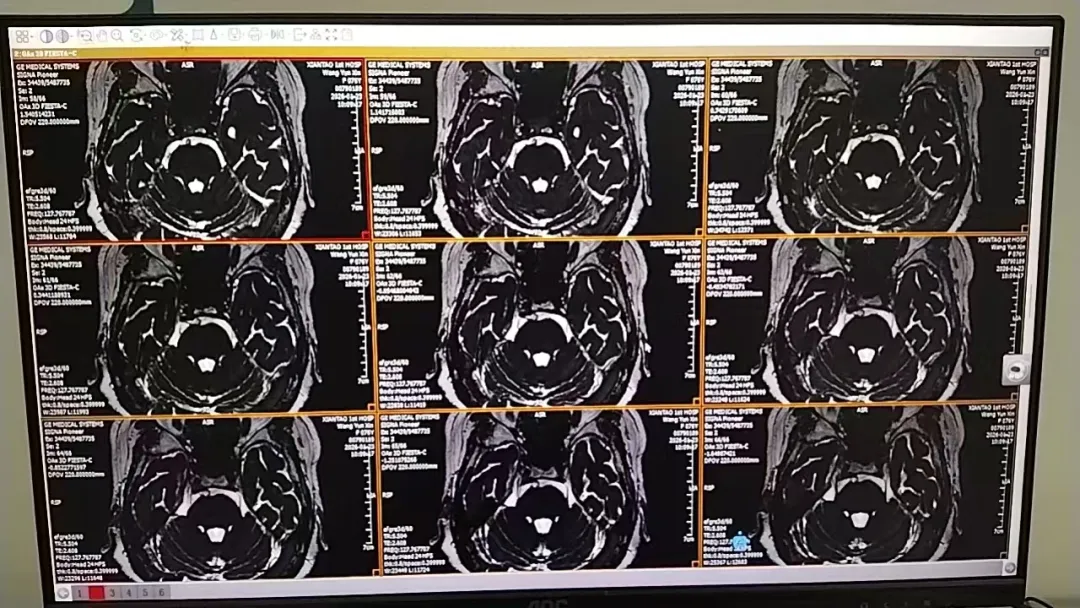

为求彻底解决,家人带她来到市一医就诊。神经外科团队为其完善三叉神经MRI检查,结果提示其右侧三叉神经脑池段小血管紧邻骑跨,这正是反复触发剧痛的“元凶”。患者76岁,合并高血压、房性期前收缩、频发性室性期前收缩等基础疾病,药物治疗效果也不佳,手术是唯一出路,但高龄与基础病让这条路并不平坦。